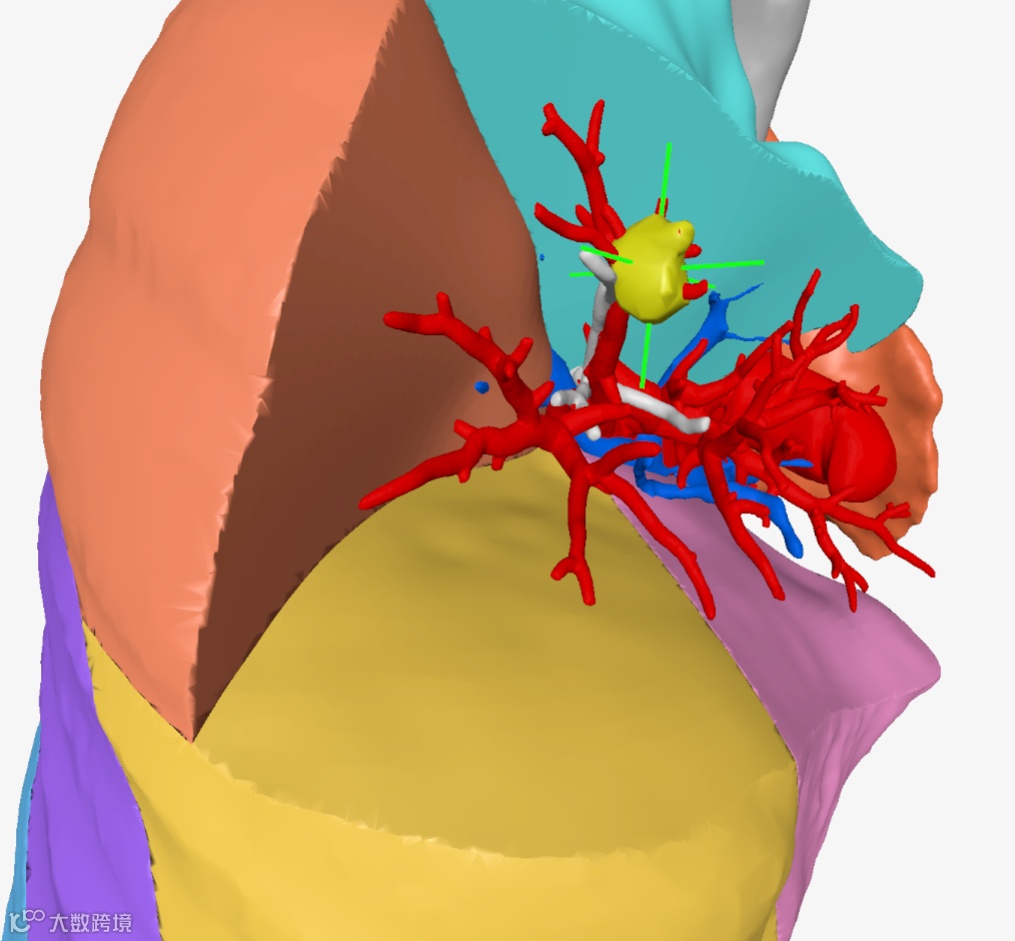

▲▲▲病变与肺叶之间关系

▲▲▲病变与肺段之间关系

▲▲▲局部细节